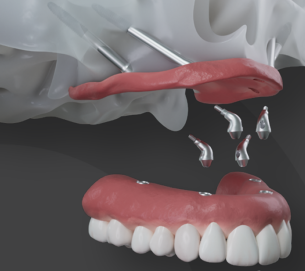

Indicados para casos extremos de reabsorção óssea, onde os implantes tradicionais não têm ancoragem, temos a grata satisfação em oferecer a reabilitação com os implantes zigomáticos. Isto é possível através da nossa equipe especializada de cirurgiões bucomaxilofaciais e médicos, que devolvem o sorriso fixo mesmo nos casos limítrofes.